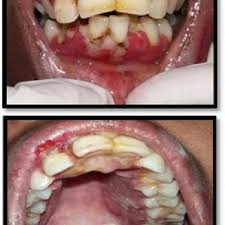

Trench Mouth The American Journal Of Medicine

Trench Mouth The American Journal Of Medicine from els-jbs-prod-cdn.jbs.elsevierhealth.com

Herpetic gingivostomatitis is often the initial presentation during the first (primary) herpes simplex infection. Gingivostomatitis is a combination of gingivitis and stomatitis, or an inflammation of the oral mucosa and gingiva. Herpes simplex virus infections may be caused by two virus genotypes: Herpes simplex virus two further conditions, seen especially in children, are herpetic gingivostomatitis and herpetic whitlow. The herpes simplex virus is categorized into 2 types: